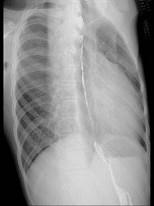

问题 21岁男性患者,劳累后心悸、气促5年,听诊第2肋间有喷射性杂音,胸部三位片如图所示,你认为正确的描述和答案是 ( )

选项 A、考虑房间隔缺损 B、考虑室间隔缺损 C、右前斜位示左心房食管压迹未见明显加深 D、左、右前斜位示右心房段延长 E、后前位示心脏左移,主动脉结缩小,肺动脉段突出

答案 ACDE